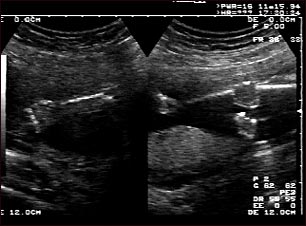

Ultrasonido normal - brazos y piernas del feto

Ultrasonido normal a las 19 semanas de gestación en el cual se aprecia el tipo de proyección de la imagen en pantalla dividida que la madre puede observar durante el procedimiento, o que el técnico puede imprimir. Se observan el brazo izquierdo (al lado izquierdo de la pantalla) y las extremidades inferiores (al lado derecho de la pantalla) y las áreas blancas dentro de brazos y piernas son los huesos en formación.